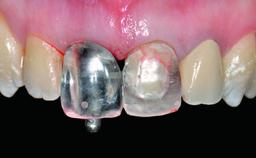

Replacement of an Ankylosed Central Incisor with a Gingival Recession: Tooth Extraction with Socket Grafting and Late Implant Placement with Simultaneous Contour Augmentation

In 2008, a healthy 15-year-old female, non-smoking patient presented at our clinic with a major esthetic problem of tooth 21. Her dental history revealed that the tooth had been avulsed by trauma years before. As a result, the replanted and temporarily splinted tooth had ankylosed and was in severe apical malposition. The ankylosed tooth exhibited a significant gingival recession that disturbed the patient greatly. Due to the patient’s low age and with her skeletal growth not completed, periodic follow-up visits were scheduled to monitor the situation until the patient was old enough for implant therapy.

Placement Protocol Early or late implant placement

Provisional Implant-Supported Prosthesis Prosthodontic margin > 3 mm apical to mucosal margin Prosthodontic margin > 3 mm apical to mucosal margin